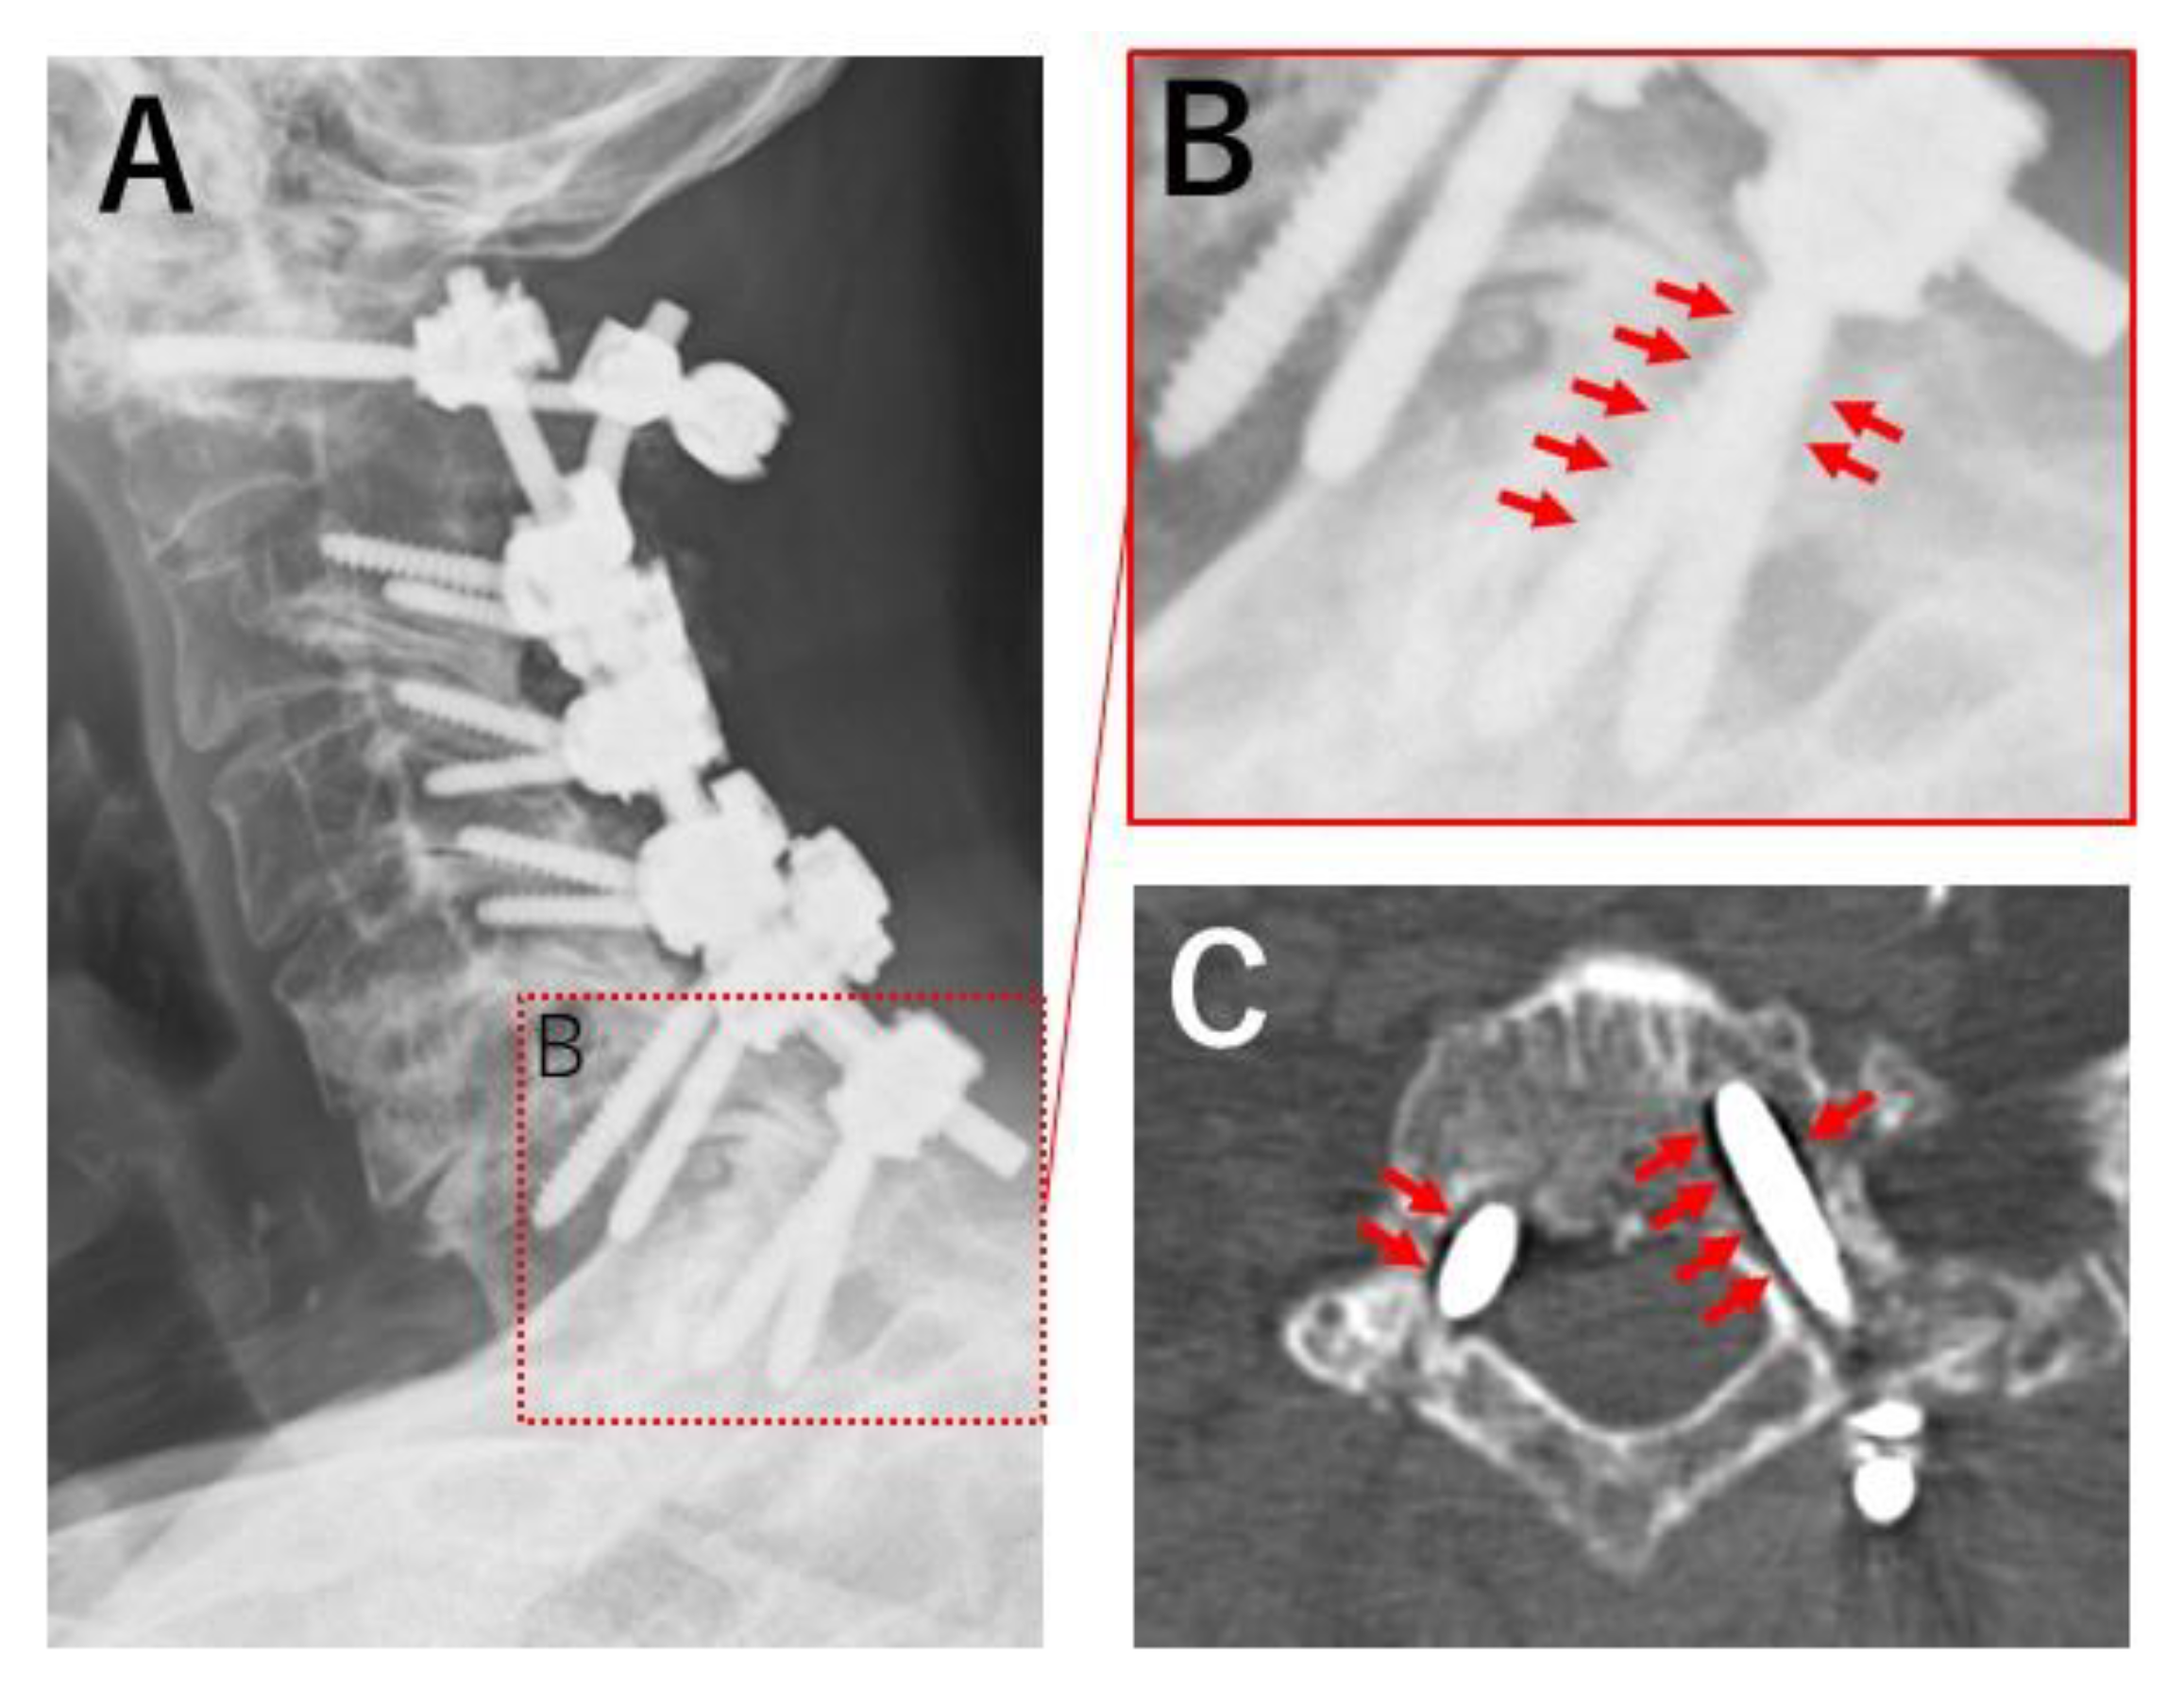

- Nagashima, K.; Koda, M.; Abe, T.; Kumagai, H.; Miura, K.; Fujii, K.; Noguchi, H.; Funayama, T.; Miyamoto, T.; Mannoji, C.; et al. Implant failure of pedicle screws in long-segment posterior cervical fusion is likely to occur at C7 and is avoidable by concomitant C6 or T1 buttress pedicle screws. J. Clin. Neurosci. 2019, 63, 106–109. [Google Scholar] [CrossRef]